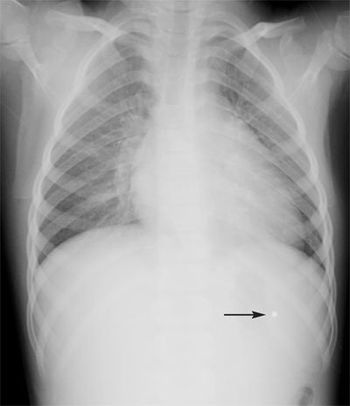

A 5-year-old girl was brought to the emergency department after she was injured during a drive-by shooting. She had 5 small entry wounds: 2 in the arm, 2 in the buttocks, and 1 in the left torso. Radiographs confirmed that a piece of pellet had entered her upper torso but was not in the lung or causing any problem.